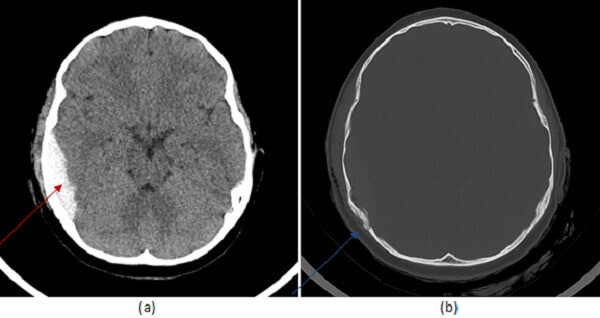

Diagnosis: Epidural Hematoma

Figure 1: (a, red arrow) noncontrast head CT demonstrates a hyperdense extra-axial collection convex to the brain parenchyma which does not cross suture lines. It is associated with a fracture of the parietal calvarium (b, blue arrow).

Epidural hematomas are due to tears in the middle meningeal artery. They tend to be convex to the brain parenchyma, do not cross suture lines in the calvarium and may rapidly expand (under arterial pressure) sometimes in a delayed fashion resulting in a sudden neurologic decompensation hours after the trauma has occurred. By comparison, subdural hematomas are lentiform in shape and can cross suture lines. Subarachnoid hemorrhage occurs between pia and arachnoid layers and unlike subdural or epidural hemorrhage extends within the sulci of the brain parenchyma. It is important to look at the attenuation of the epidural hematoma, for epidurals with mixed density – the “swirl” sign- can be an indication of active or ongoing bleeding and bode a worse prognosis.